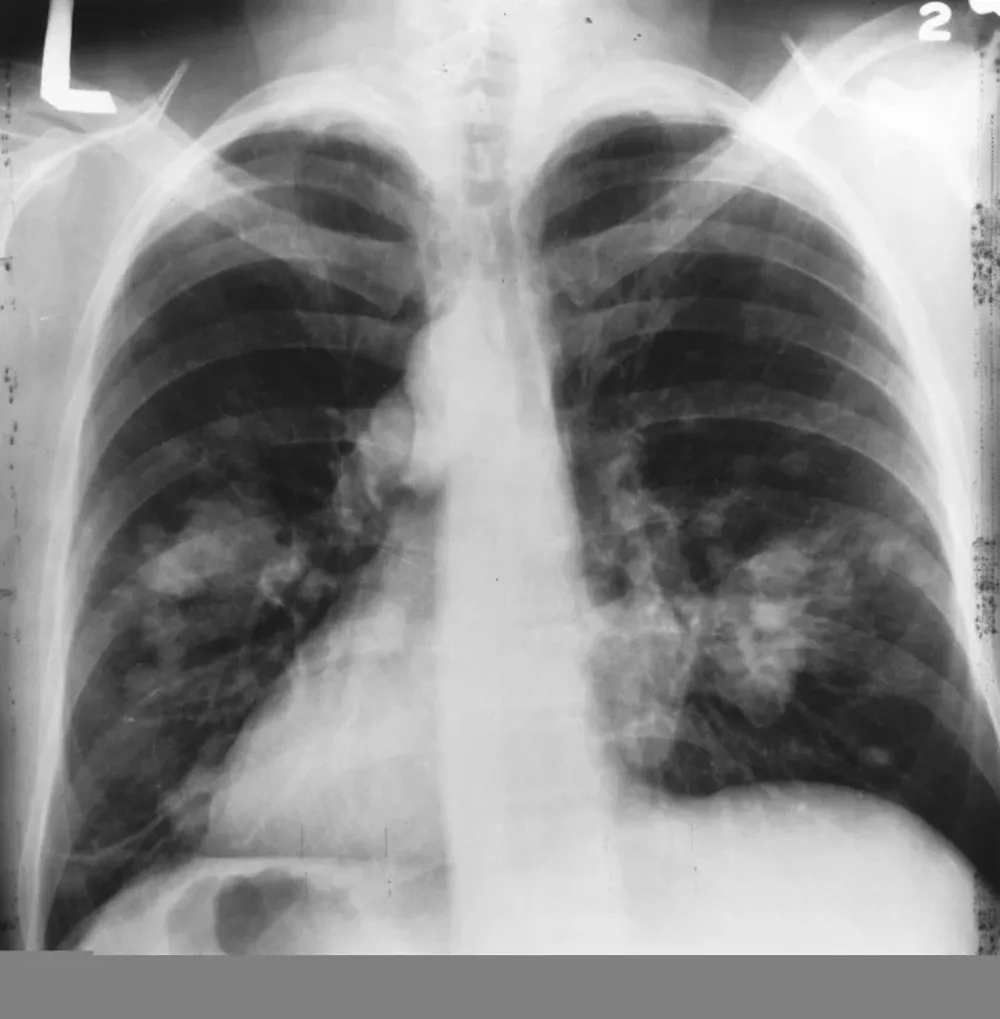

La medicina ha encontrado una nueva forma de extender la expectativa de vida de los pacientes de cáncer de pulmón. Se trata de los medicamentos de inmunoterapia, que al ser aplicados de forma previa a las cirugías para extraer el cáncer ayudan a debilitar los tumores, así como a evitar su expansión a otras partes del cuerpo.

El uso de estos tratamientos llega luego de un estudio en el que se analizó a 20 pacientes que padecían cáncer de pulmón. Un año después de iniciar el tratamiento y de ser operados, 16 de ellos seguían con vida y la enfermedad era indetectable. Dos más la tenían de nuevo pero fue erradicada al retomar el tratamiento, mientras que solo uno de los dos restantes falleció a causa del cáncer; el otro fue por una lesión en la cabeza.

Estos medicamentos "rompen" el tumor, y lo atacan directamente, y son utlizados principalmente en pacientes con casos avanzados de la enfermedad. "Cuando los cirujanos los abren, encuentran que los tumores están derretidos. Se los come como un pac-man"; explicó Herbst.